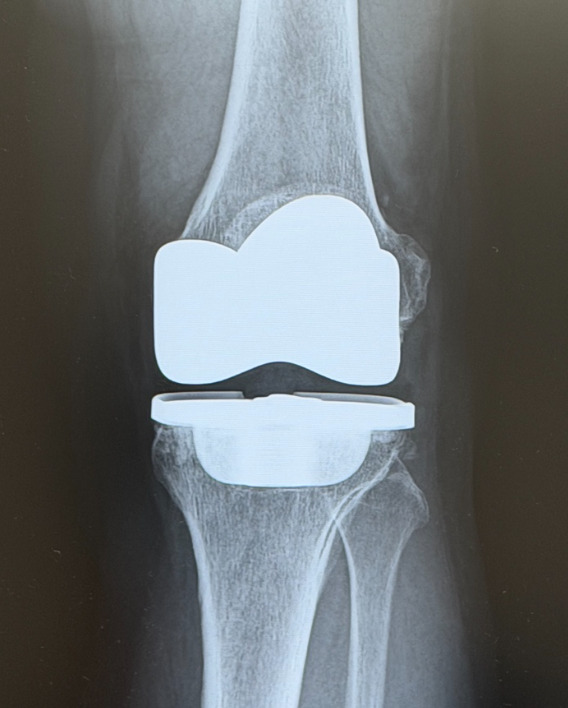

関節リウマチの手術療法

薬物治療を行っても関節破壊や変形が進行した場合には、人工関節置換術や関節固定術などの手術を検討します。ただし、現在は早期治療が普及し、手術に至るケースは以前より減少しています。